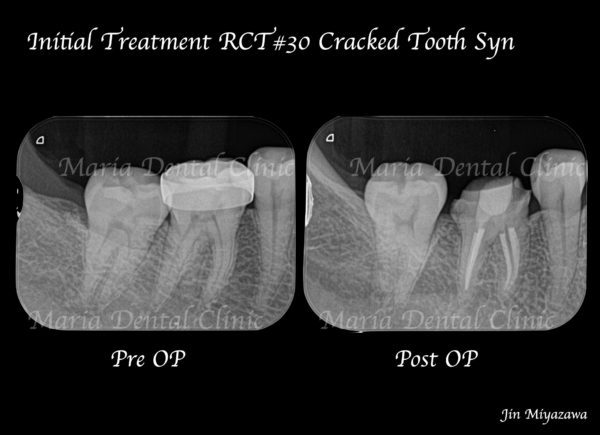

|治療詳細画像_4-1.png)

|治療詳細画像5.png)

クラックトゥースの原因歯を特定できた場合、治療の選択肢は下記の2つです。

① 歯髄を保存したまま全部被覆冠(※)を装着する。

② 神経を除去した後、全部被覆冠を装着する。

※全部被覆冠:歯冠全体を覆う被せ物

① の場合、神経は残すことができますが、将来的にクラックが進行した際、歯髄炎に罹患し、強い痛みが出る可能性があります。

② の場合、神経を取ることになりますが、クラックが進行しても歯髄炎を回避することができます。

将来的にクラックがどのくらいのペースで進行していくか、もしくは完全に歯の破折を予防できるかは不透明なため、この選択は重要であると考えます。

今回の患者様は、精密根管治療を行うことで、治療の成功率が比較的高いうちに処置を完了させる②の治療を選択されました。精密根管治療は必要最低限の歯質削除量で治療が完了することから、有意義な選択と言えます。